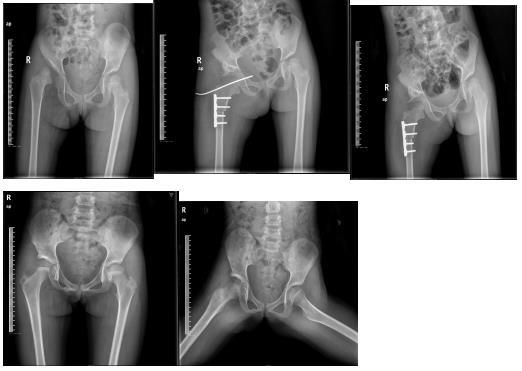

我科是区内少数能开展手术治疗发育性髋关节的科室,能运用髋人字石膏外固定,Salter、Pemberton髋骨截骨等治疗发育性髋关节脱位,技术达到区内领先水平,在国内享有较高的声誉。

右髋关节发育性脱经髋人类位石膏外固定保守治疗,保守治疗后随访5年股骨头与髋臼匹配无再脱位,股骨头发育良好,无坏死。

右髋关节发育性脱位行Pemberton髋骨截骨,股骨短缩旋转术后随访5年,股骨头与髋臼发育良好。